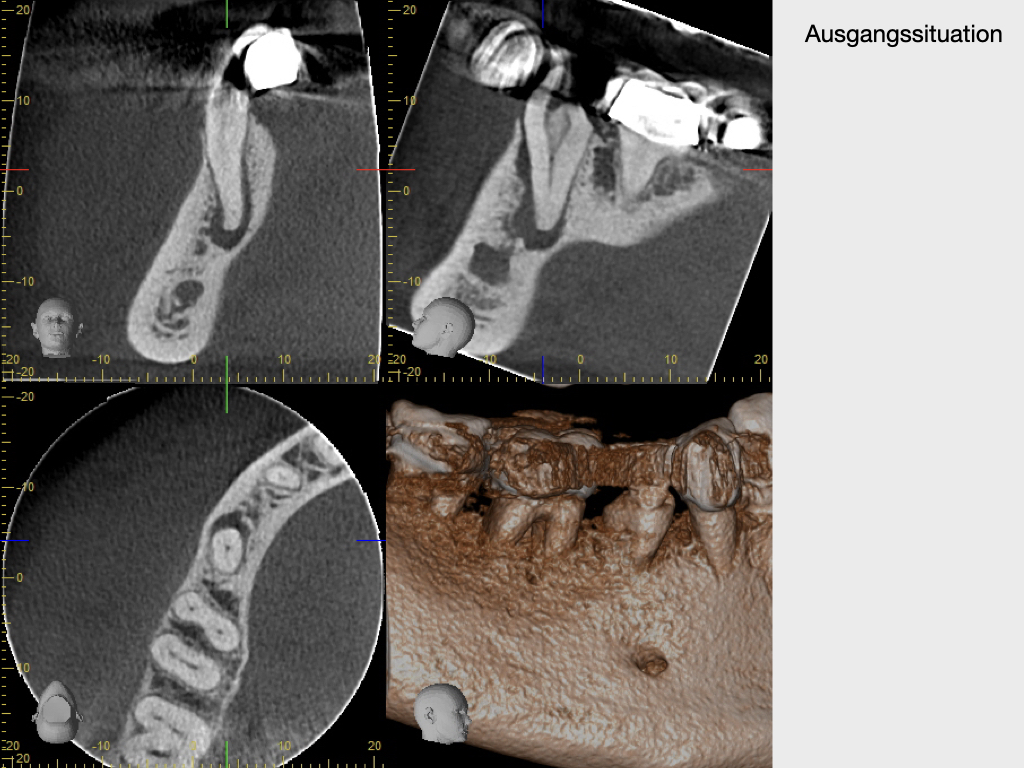

lateraler Kanal.003

Lateraler Kanal